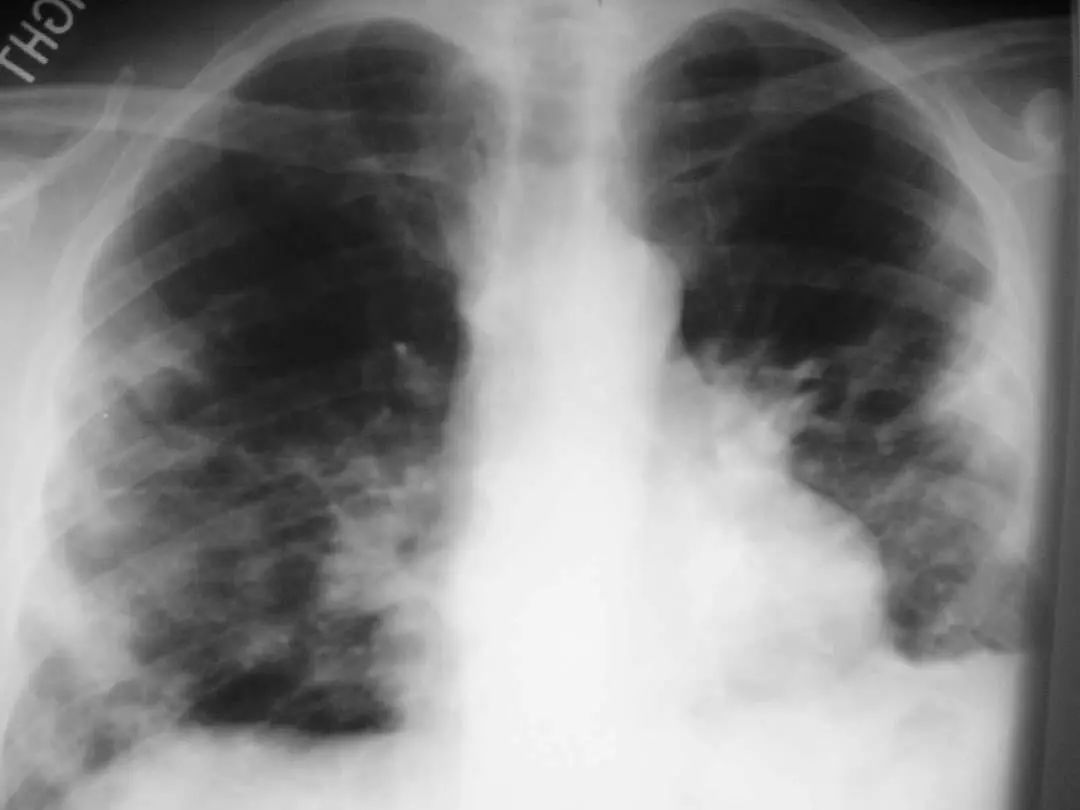

图1.1 细菌性肺炎。右上叶肺炎患者的放射影像。胸廓前后径增大,提示有慢性阻塞性肺疾病(COPD)。

图1.2 细菌性肺炎。双肺下叶肺炎患者影像。

图1.3 细菌性肺炎。早期右肺中叶肺炎的影像学表现。

图1.4 53岁的严重军团菌肺炎患者。胸片显示双肺下叶致密实变。

图1.5 40岁肺炎衣原体患者。胸片显示右上、中、下叶多灶性斑片状实变。

图1.6 38岁的支原体肺炎患者。胸部X线片显示左下叶模糊不透明影。